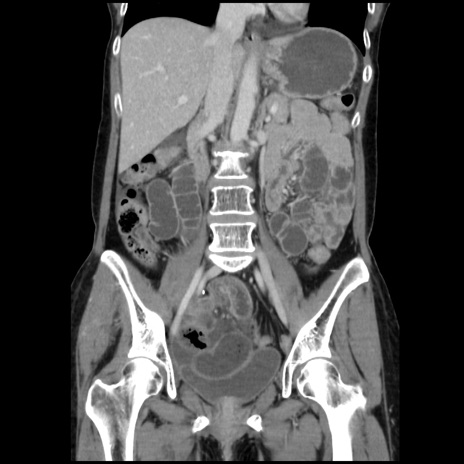

症例32(冠状断像)

【症例】40歳代 女性

【主訴】上腹部痛、嘔気・嘔吐

【現病歴】約9時間前頃から急に上腹部痛、嘔気、嘔吐が出現。改善しないため救急要請。

【既往歴】子宮頚癌(広汎子宮全摘術、放射線療法)、腸閉塞

【身体所見】腹部:平坦、軟、腸雑音亢進、上腹部を中心に腹部全体に圧痛あり。

【データ】WBC 8400、CRP 0.03